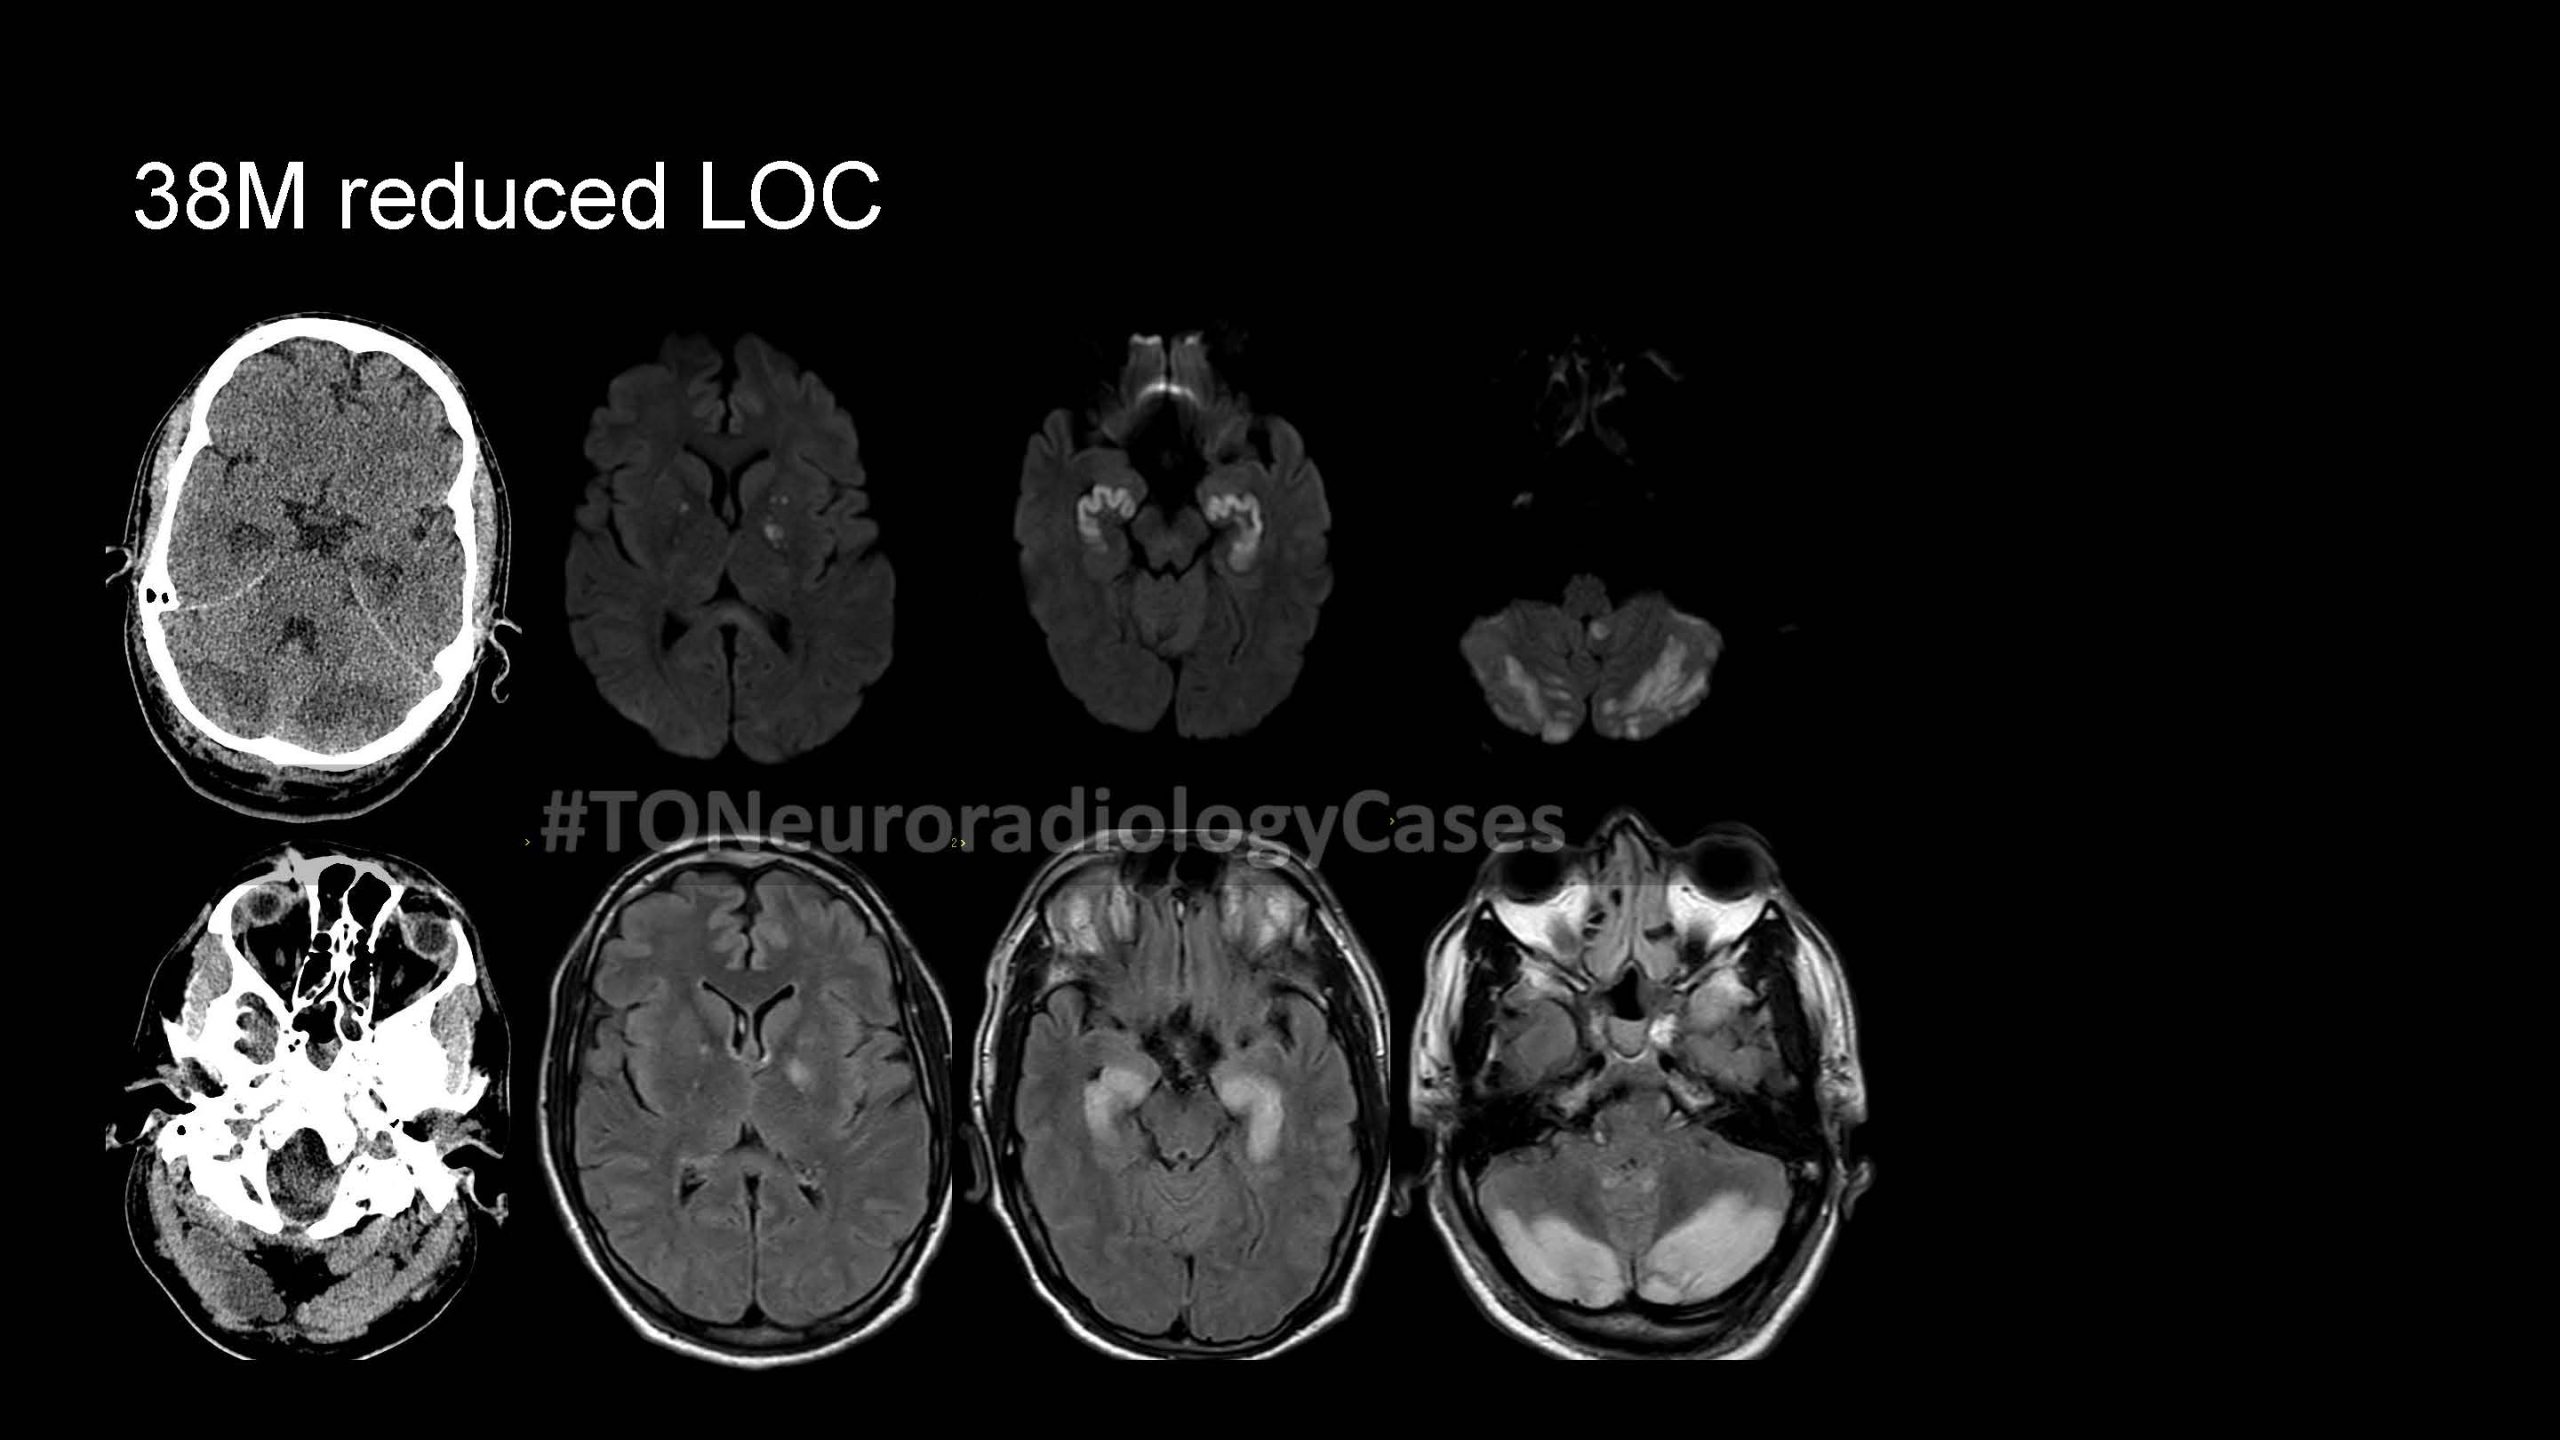

DR. AMY CHEN’S

Neuroradiology Case of the Week

@ Toronto Radiology

Over the past few years, I’ve had the pleasure of curating a “Case of the Week” contest with contributions from radiologists across the city, designed to challenge and engage our neuroradiology fellows at the University of Toronto. This collection showcases a range of neuroradiology cases from our city and have been a fun part of our fellow’s educational experience. I am excited to share this resource with a wider audience, now featured on our Toronto Radiology departmental website.